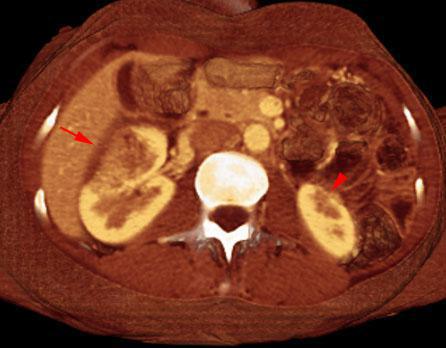

Pielonefritis aguda 1